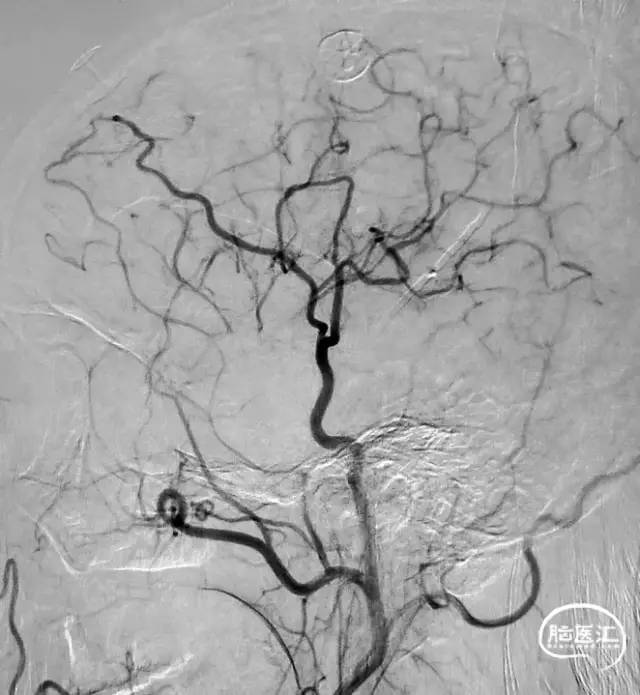

图1 从大脑后动脉(PCA)到大脑前动脉(ACA)的软脑膜侧支;A. 椎动脉注射侧位图显示ACA和PCA区域之间的逆行血流(PCA→ACA顶枕支)延伸到皮质边界区;B. 经后胼胝体周动脉经中央沟的血供。[7]